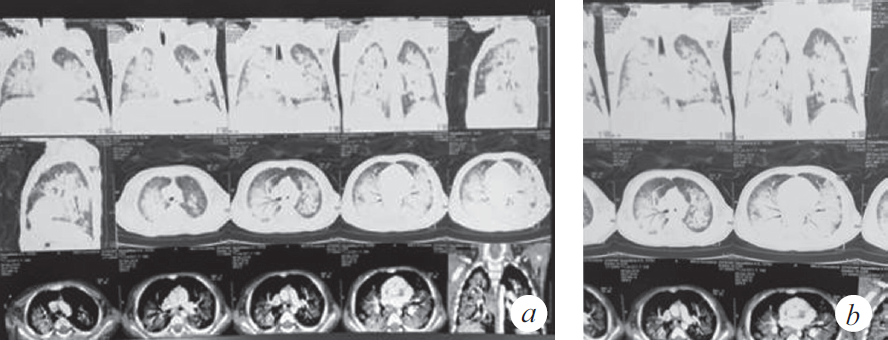

Через 2 нед. госпитализации в ОРИТ у ребенка наросли клинические и параклинические проявления госпитальной пневмонии (лихорадка, повышение С-реактивного белка до 39,7 мг/л), высев грибов рода Candida, Staphylococcus aureus — из верхних дыхательных путей; Еnterococcus faecalis, Еnterococcus fecuim, Klebsiella pneumoniae — из мочи, кала. На контрольной КТ: отрицательная динамика в виде увеличения консолидации в периферических отделах легких (рис. 2), клиническая картина не изменилась. На фоне антибактериальной терапии широкого спектра действия дыхательная недостаточность не прогрессировала, явления инфекционного токсикоза были купированы, кашель отсутствовал. Максимальная оценка по шкале SOFA (Sequential Organ Failure Assessment) 3 балла.

Рис. 2. Компьютерная томограмма органов грудной клетки (через 5 нед. от дебюта заболевания) (a). Признаки диффузного интерстициального повреждения легких. Отмечена отрицательная динамика в виде увеличения консолидации в периферических отделах легких (b)

Fig. 2. CT of the chest organs (5 weeks after the onset of the disease) (a). Signs of diffuse interstitial lung disease. Negative dynamics in the form of increased consolidation in the peripheral parts of the lungs (b)